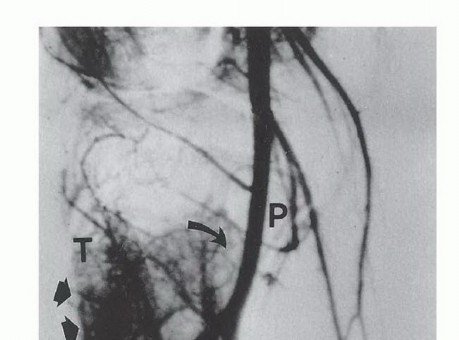

- تصوير الأوعية ثنائي المستوى (Digital Subtraction Angiography - DSA): في بعض الحالات، يُستخدم لتقييم إمداد الدم للورم وعلاقته بالأوعية الرئيسية، خاصة عند التخطيط للجراحات المعقدة.

* الشريان المأبضي (Popliteal Artery) وفروعه: يمر خلف الركبة ويُغذي الجزء السفلي من الساق والقدم.